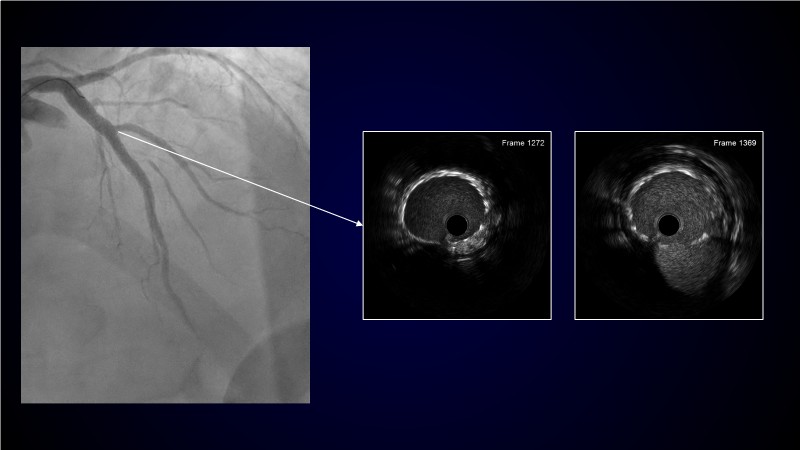

Calcified coronary lesions are a major challenge in PCI. This PCRGulf-GIM 2025 session showcases a complex case with intravascular imaging, highlighting how IVUS 123 guides each step.

From planning the procedure and understanding calcium distribution, to lesion preparation with modern modification tools, and post-PCI assessment to confirm stent expansion and detect complications, this session demonstrates practical, imaging-driven strategies.